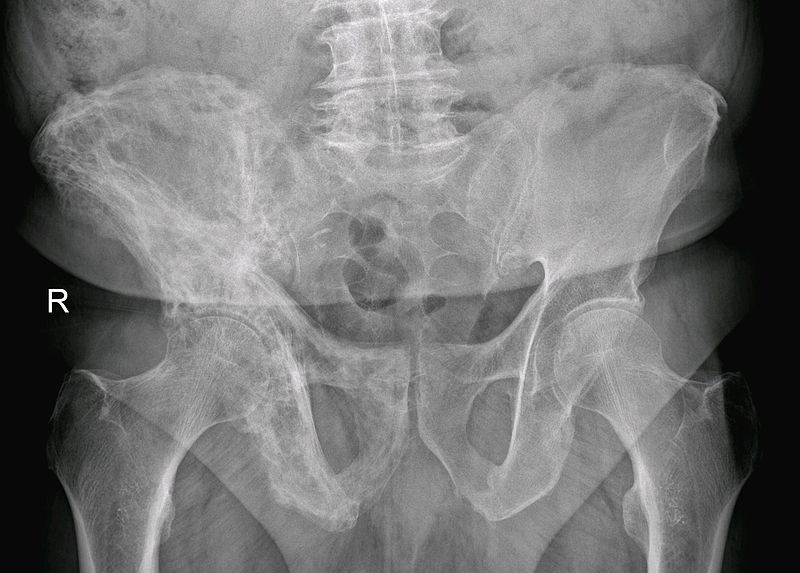

Metastatic Tumors to the Bone

Primary cancers are less frequent than metastatic tumors to the bone.

Metastatic tumors to the bone typically show osteolytic, punched-out lesions on X-ray.

Notably, metastatic prostate cancer to the bone produces osteoblastic lesions.